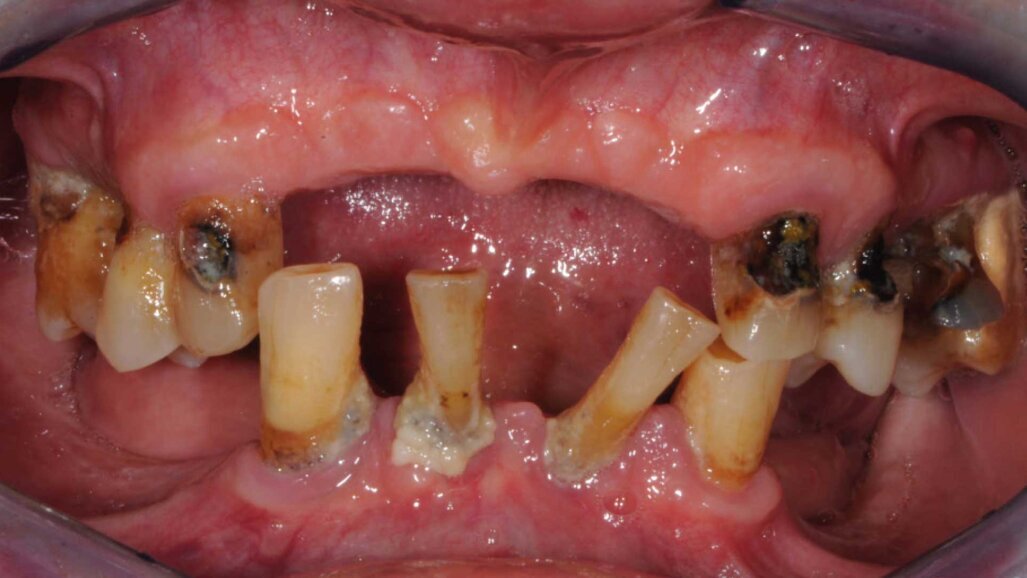

Il paziente si presentò alla nostra osservazione lamentando una diminuzione della capacità masticatoria. All’osservazione clinica e radiografica (Figg. 1, 2) si evidenziava la mancanza di numerosi elementi dentari e di una diffusa malattia parodontale, il tutto complicato dalla presenza di carie destruenti su tutti gli elementi dentari con migrazione degli stessi. Lo spostamento dei denti aveva portato a perdita della dimensione verticale e di tutti i punti di riferimento per la ricostruzione della dentatura.

Al paziente fu spiegato che la strategia migliore consisteva nell’estrazione di tutti gli elementi dentari e l’inserimento di sei impianti in ogni arcata dentaria e successivamente il ripristino delle arcate con due protesi tipo Toronto. Si decise di non estrarre subito i quattro canini perché sarebbero serviti per stabilizzare le mascherine chirurgiche durante la chirurgia. Lo studio del caso e la sua realizzazione fu fatta con metodo analogico. Due modelli in gesso furono montati alla giusta dimensione verticale e fu realizzato il montaggio dei denti per visualizzare il risultato finale (Fig. 3). Dal montaggio dei denti furono realizzate le mascherine chirurgiche che sarebbero state utilizzate per gli esami radiografici tridimensionali e avrebbero guidato il posizionamento degli impianti durante la chirurgia. All’esame radiografico tridimensionale (Figg. 4-7) si notava la presenza di una quantità esigua di osso coronalmente ai seni mascellari e al nervo alveolare inferiore. Si decise di inserire impianti extracorti 4,5 mm di lunghezza in queste zone, per evitare sia impianti inclinati sia cantilever molto estesi. Lo studio della scala dei grigi, o scala Hounsfield, mostrava una densità ossea tale da consentire il carico immediato anche in queste zone. Ovviamente sarebbe stata necessaria la conferma intra-operatoria valutando clinicamente la compattezza dell’osso tramite la fresatura.